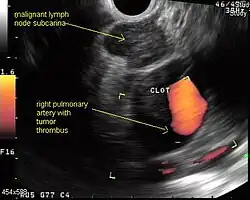

A metaanalysis published in 2007, based on 1,201 cancers in 18 high-quality clinical trials carefully selected by predefined criteria from the literature, systematically examined the performance of EUS-guided FNA in NSCLC staging. Two scenarios were considered: the setting of enlarged lymph nodes on CT (suggestive but not diagnostic of cancer), and the obverse scenario of an absence of lymph node enlargement on CT (suggestive but not diagnostic of no cancer).[28] Overall, in both settings, minor complications were reported in 0.8% of procedures; no major complications were recorded. EUS-FNA in enlarged discrete mediastinal lymph nodes had an excellent pooled sensitivity (8 studies) of 90% (95% CI, 84 to 94%) and specificity of 97% (95% CI, 95 to 98%). EUS-FNA in the setting of no enlarged mediastinal lymph nodes on CT had a pooled sensitivity (4 studies) of 58% (95% CI, 39 to 75%) and specificity of 98% (95% CI, 96 to 99%). Although this sensitivity (58% in CT-negative disease) might on first consideration seem disappointing, if EUS is performed as a staging test it can help avoid more invasive staging procedures, or surgery, if positive (for the presence of cancer). In other words, an EUS that has a positive result (shows cancer) will avoid further needless surgery, whereas a result not showing cancer may be false-negative, and probably requires an excisional biopsy technique for confirmation, such as VATS or mediastinoscopy.

EUS can reliably reach the lymph node stations 5, 7, 8 and 9. In the superior mediastinum the trachea is somewhat to the right of the esophagus which makes it often possible to reach left-sided area 2 and 4 lymph nodes and, less often, right sided paratracheal lymph nodes.[33] In general, EUS is most appropriate for evaluation of the posterior inferior mediastinum while mediastinoscopy or EBUS are best for the anterior superior mediastinum. The feasibility of EUS-FNA of aorto-pulmonary space (subaortic) lymph nodes (station 5) is a major advantage of EUS. Evaluation of this station has traditionally required a paramedian mediastinotomy (Chamberlain procedure). EUS can easily sample celiac lymph nodes, which cannot be reached by the other mediastinal staging methods. In one recent study an unexpectedly high incidence of celiac lymph node metastasis (11%) was noted.[34] EUS can also be used to biopsy potential left adrenal metastases, whereas the right adrenal gland is mostly inaccessible.[35]

The potential utility of EUS-FNA in restaging of the mediastinum in patients who have undergone chemotherapy and radiotherapy for N2 or N3 disease is under investigation. The underlying idea is that initially advanced cancers, previously too extensive for surgery, may have responded to chemotherapy and radiation so much that they now may be operative candidates. Rather than immediately proceeding to thoracotomy based on CT or PET results, which could lead to an "open and close" thorax surgery, restaging, including invasive staging, may deselect non-responders, missed on imaging tests alone. If the initial mediastinal staging included a mediastinoscopy, most surgeons try to avoid a repeat mediastinoscopy after radiation treatment because of scarring. Although restaging by PET and CT scanning may help to provide targets for biopsies, the concept is that even PET-negative mediastinums need to be sampled. In N2 disease, EUS-FNA and EBUS-FNA appear to offer the best risk-benefit ratio in these patients.[36]

EUS-FNA and EBUS-FNA are complementary techniques. EUS has the highest yield in the posterior inferior mediastinum, and EBUS is strongest for the superior anterior mediastinum. Some lymph node stations can only be accessed by one method and not the other (for example, station 2 and 4 L and 3 are hard or impossible to see by EUS, stations 5 and 8 cannot be biopsied by EBUS). Together, EBUS and EUS cover the entire mediastinum (except possibly station 6) and complete mediastinal staging should be possible with a combination of these two procedures. This combination could conceptually eliminate the need for most surgical mediastinoscopies and in fact be more comprehensive.

When combined, this approach has been termed "complete medical mediastinoscopy." EUS-FNA with EBUS may allow near-complete, minimally invasive mediastinal staging in patients with suspected lung cancer [42]